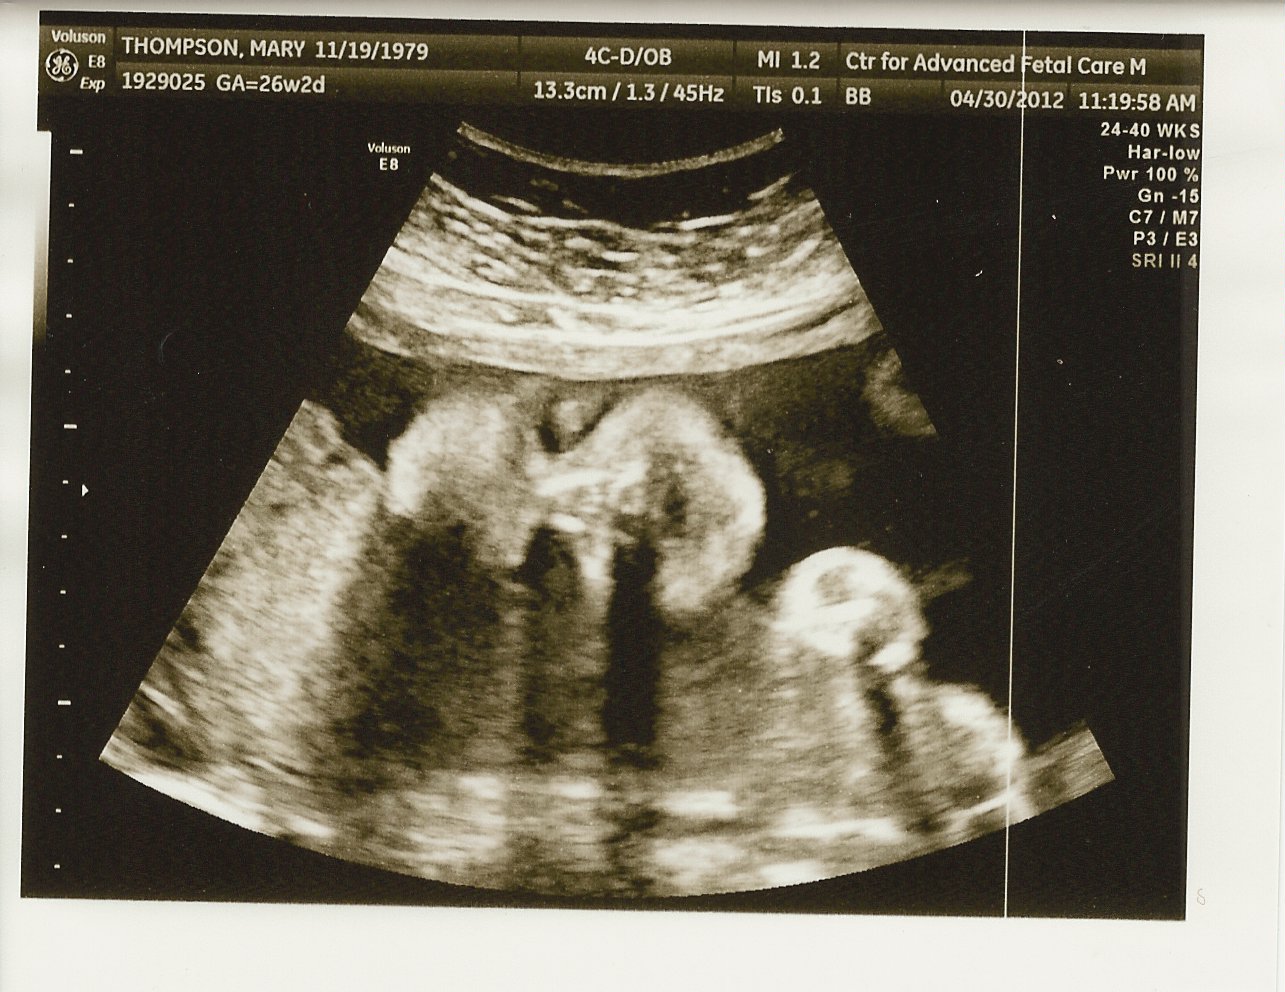

Here's some of the most recent u/s pics:

One of my first 3D pics...I'm sucking on my fingers

Still love waving to the camera

Profile at 25 weeks, sucking on my fingers

Yup, still a boy!

Smiling for the camera (26 weeks)